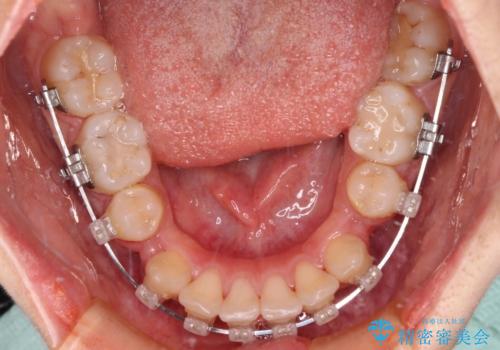

- 咬み合わせと、前歯のデコボコや八重歯、飛び出した口元を気にして来院された患者様です。

上顎は歯列不正が強く、右側臼歯部の咬み合わせは歯1本分ずれている状態でした。

補助装置を用いて奥歯の咬み合わせを改善しながら歯列を後方に移動させ、上下左右第一小臼歯を4本抜歯することで八重歯や口元の突出感を改善することとしました。

奥歯の咬み合わせの不正が顕著であったため、表側のワイヤー装置を選択して矯正治療を行うこととしました。